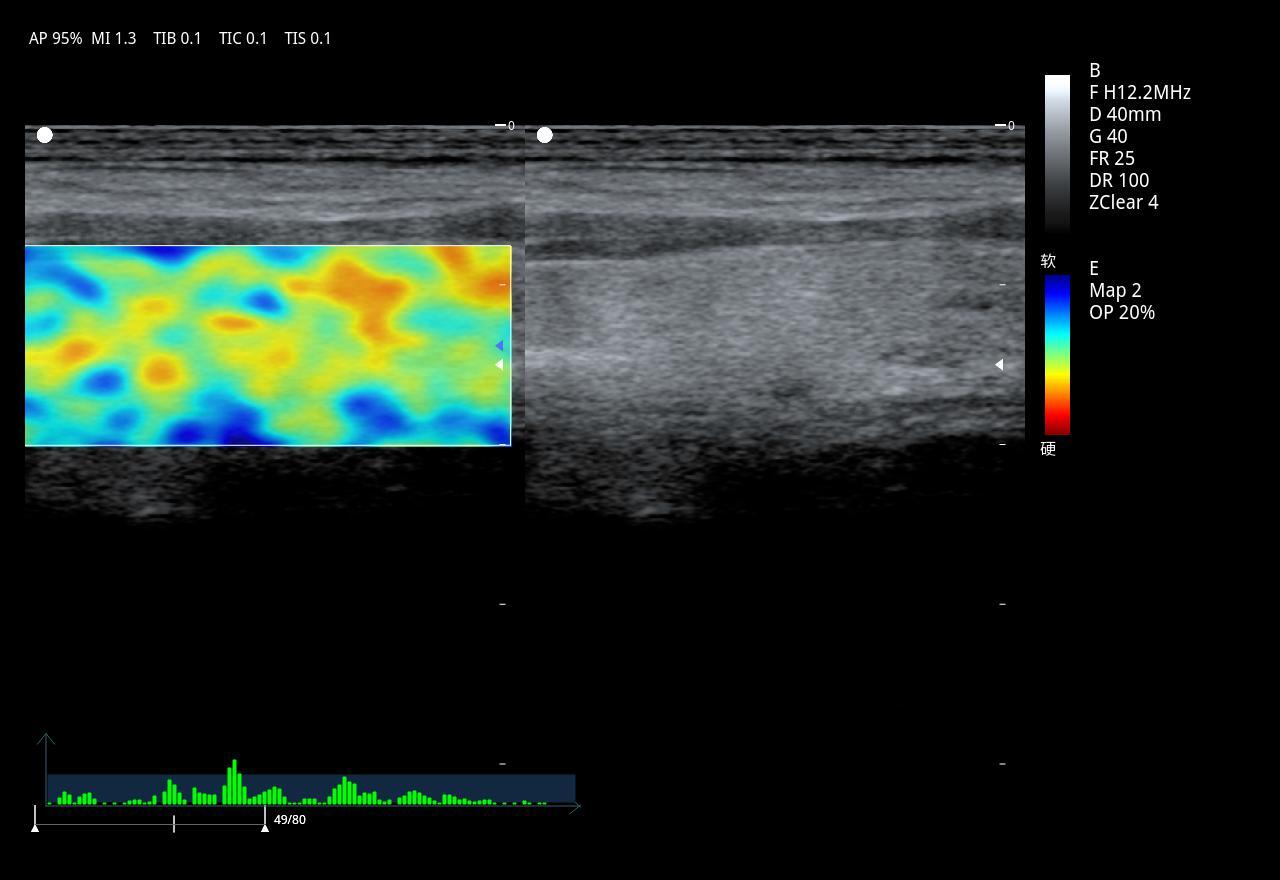

DMU27 Full Digital Color Doppler Ultrasonic Diagnostic Scanner For Human Being

1.Ergonomic Design:1) 185mm Adjustable height ofcontrolpanel2) 21.5 medical LCD monitor 3)13.3 high sensitivitytouch screen 4)Optimized control panel5)Optimized TGCArea6) 4 universal transducer connectors7)Cable Management2.Techno...

2.Technologies:

Pulse Inverse Harmonic Imaging:PIHI,PIHI reduces the distortion generated by the fundamental wave,and greatly improve the signal-to-noise ratio

Speckle Reduction Imaging:SRI technology significantly reduces the unwanted speckle,providesenhanced tissue boundary

3.Spatial Compound Imaging:SCI provides bettercontrast resolution,reduces the speckle noise and smoothes the imaging of homogeneous tissue